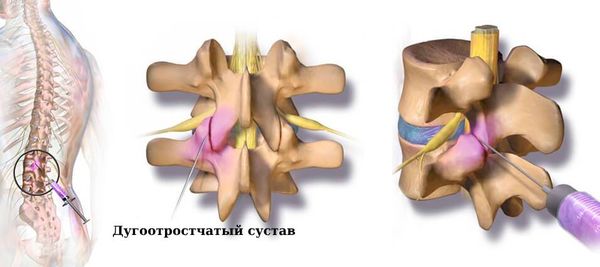

Остеоартрит фасеточных суставов: медицинские снимки и схемы